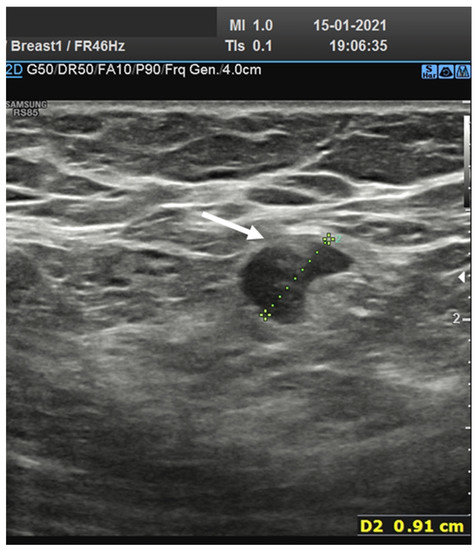

In total, four nodes (6.9%) showed huge reduction and displacement of the echogenic hilum and round or oval shape (Figure 4).

Figure 4.

(a) Hypoechoic lymph node round shape without hilum (arrows) in laterocervical side; (b) Hypoechoic lymph node oval shape without hilum (arrow) in laterocervical side; (c) Axillary small hypoechoic lymph node oval shape without hilum (arrow).